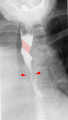

Aberrant right subclavian artery at angiography.

Tape-like impression of the esophagus caused by aberrant subclavian artery. Below (arrows) narrowing of the esophagus by a tumor that is causing the swallowing problems.